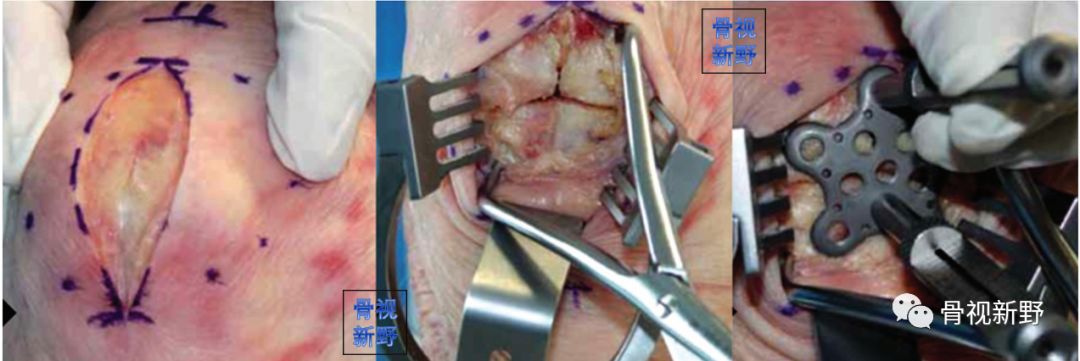

篮状钢板+编织缝合

最早在2006年,Matejcic等用篮状钢板进行髌骨粉碎骨折的固定,获得良好效果。

篮状钢板(basket plate),1988年由Branimir Smiljanic 医生设计,主要用于髌骨下极的粉碎骨折。

篮状钢板有利于收集粉碎骨折块、特别是下极粉碎骨折。该钢板有四个钉孔,半螺纹松钉打入对侧骨块以获得骨碎块间的加压。

术中所见